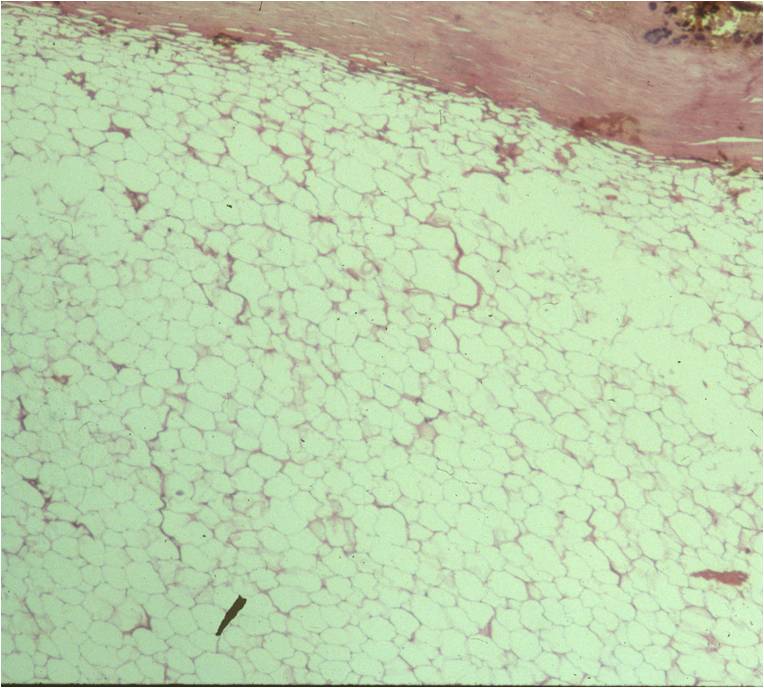

Microscopic

• Mature fat cells with small, uniform, eccentric nuclei

• Nucleus compressed against the periphery of the cell membrane by a fat vacuole

• No mitotic figures

• Can have areas that undergo fat necrosis

• Muscle fibers interspersed amongst mature adipocytes (intramuscular lipomas)

• Other components

• Fibrous tissue

• Myxoid tissue

• Blood vessels

Fig. 4 & 5: Microscopic Pathology of a lipoma shows a homogeneous structure in low and high magnification with a uniform cell pattern and peripheral compressed nuclei barely discernible. Mature adipocytes. No mitoses.